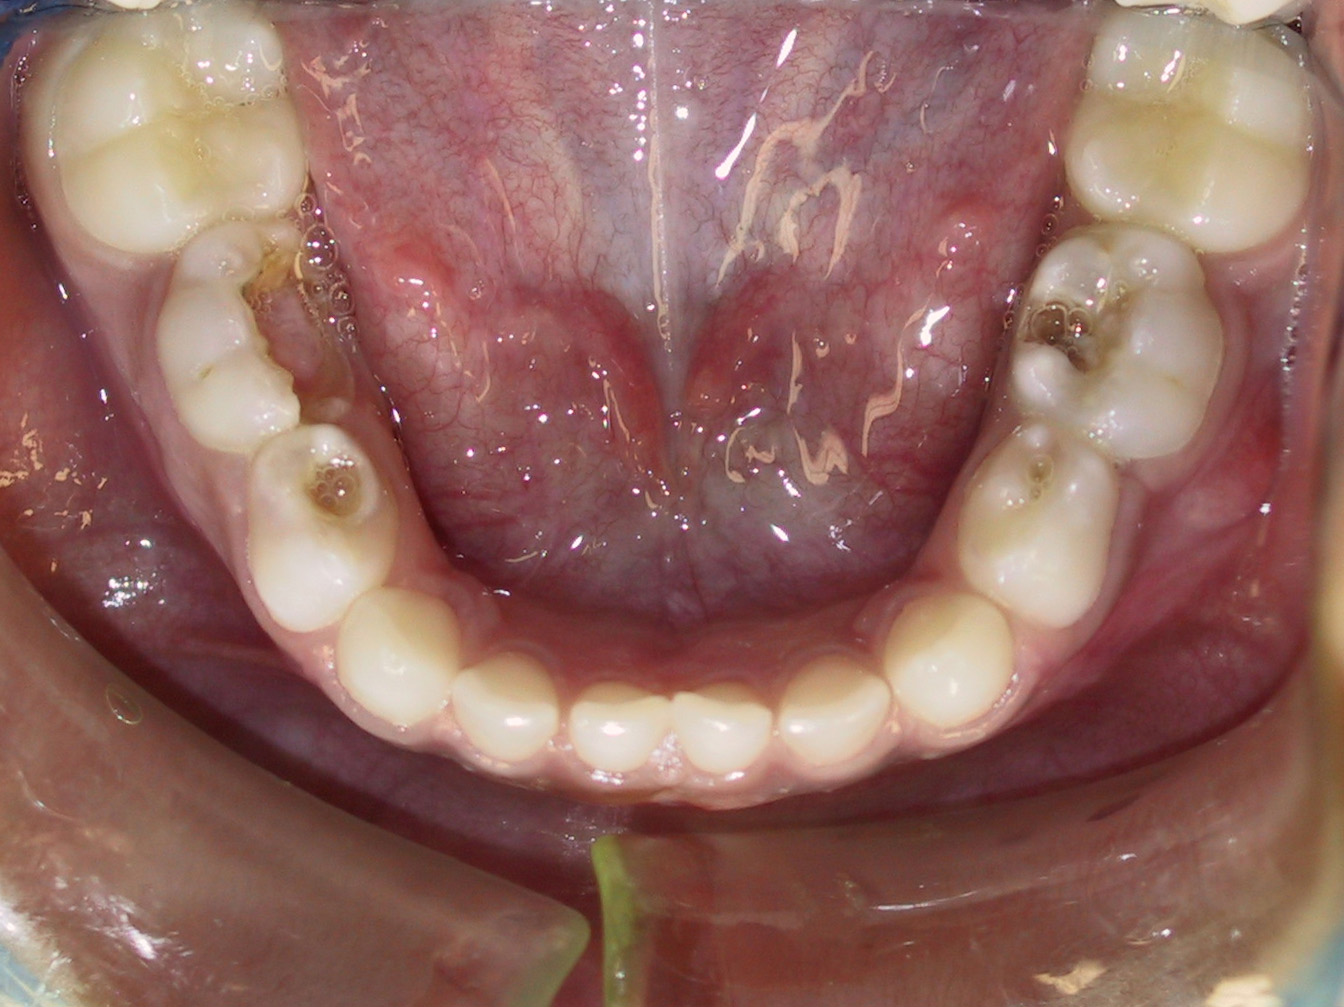

So often we think of “baby” or primary teeth as not being important. However, the complete opposite is actually true! Remember, those primary teeth are holding everything in place and preparing the mouth for the permanent or “adult” teeth that will come in later. If primary teeth are lost too early, due to decay or other reasons, your child’s smile loses that space holder. Permanent teeth can then come in misplaced or misaligned. Also, if a primary tooth is left untreated with ongoing decay, it can cause infection, which can then cause damage to the permanent, unerupted tooth coming in behind it. So even though these primary teeth will eventually fall out, you still want to make sure to take care of any current cavities on those baby teeth!